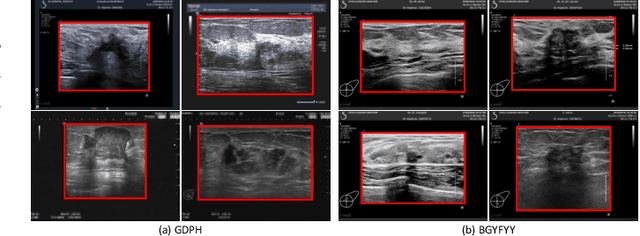

Abstract:Ultrasonography is an important routine examination for breast cancer diagnosis, due to its non-invasive, radiation-free and low-cost properties. However, it is still not the first-line screening test for breast cancer due to its inherent limitations. It would be a tremendous success if we can precisely diagnose breast cancer by breast ultrasound images (BUS). Many learning-based computer-aided diagnostic methods have been proposed to achieve breast cancer diagnosis/lesion classification. However, most of them require a pre-define ROI and then classify the lesion inside the ROI. Conventional classification backbones, such as VGG16 and ResNet50, can achieve promising classification results with no ROI requirement. But these models lack interpretability, thus restricting their use in clinical practice. In this study, we propose a novel ROI-free model for breast cancer diagnosis in ultrasound images with interpretable feature representations. We leverage the anatomical prior knowledge that malignant and benign tumors have different spatial relationships between different tissue layers, and propose a HoVer-Transformer to formulate this prior knowledge. The proposed HoVer-Trans block extracts the inter- and intra-layer spatial information horizontally and vertically. We conduct and release an open dataset GDPH&GYFYY for breast cancer diagnosis in BUS. The proposed model is evaluated in three datasets by comparing with four CNN-based models and two vision transformer models via a five-fold cross validation. It achieves state-of-the-art classification performance with the best model interpretability.